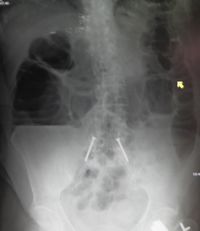

يوضح التصوير بأشعة إكس على البطن وجود انسداد بالأمعاء الدقيقة والمريض في وضع وجود مستويات متعددة من السوائل والغازات.

يوضح التصوير بأشعة إكس على البطن وجود انسداد بالأمعاء الدقيقة والمريض في وضع الوقوف. لاحظ وجود مستويات متعددة من السوائل والغازات.

من ضمن الأشياء التي يكشف عنها التصوير الإشعاعي وجود انتفاخ بالأمعاء ووجود مستويات متعددة (أكثر من ستة مستويات) من السوائل والغازات في صور الأشعة التي تؤخذ على البطن والمريض في وضع الاستلقاء على الظهر تارة والوقوف تارة أخرى.